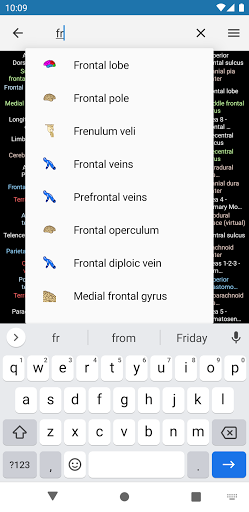

- Mudah menemukan struktur anatomi berkat pencarian indeks

*Temukan bagian anatomi Anda dengan lebih mudah berkat fitur pencarian baru yang lebih intuitif dan canggih